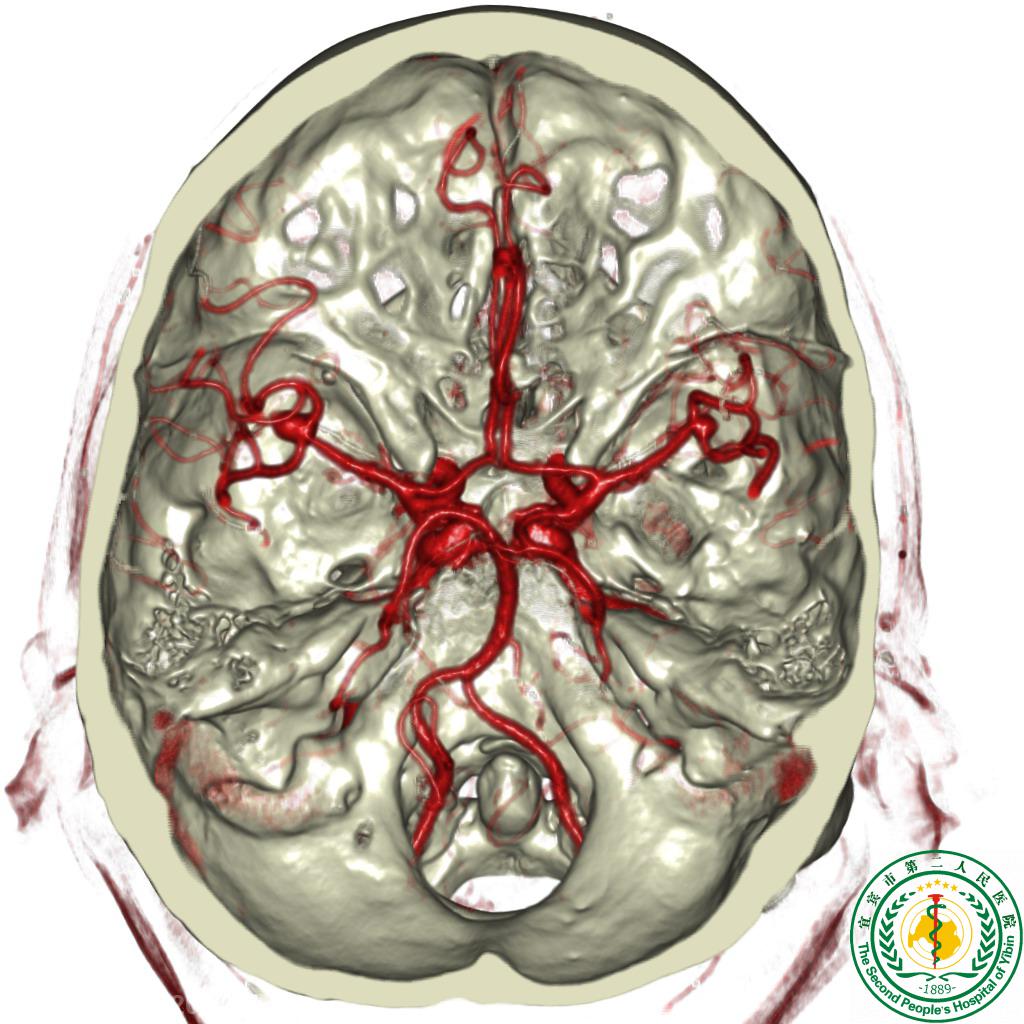

64排螺旋CT在血管成像方面有巨大优势,如冠状动脉成像、肺动脉成像、胸腹血管成像、四肢血管成像、颈、脑血管成像等,在这方面,该设备是世界顶级仪器。这些无创的检查已部分取代了传统的动脉插管造影的诊断问题,对冠心病的普查有无法比拟的优势,在检查冠状动脉有无狭窄,搭桥、支架的形态学以及心功能分析上有极大的优越性。与传统的选择性冠状动脉造影相比,CT血管成像技术能多角度显示冠状动脉主支及主要分支,并能显示常规造影不能显示的管壁结构,能准确评价斑块性质,能清晰显示冠状动脉的起源和解剖变异,指导有创性检查操作,能纠正传统造影诊断中的误区。在肿瘤诊断方面,由于它覆盖面广,各向同性,能做任意角度重建,所以能清晰显示肿瘤的位置及其与周围组织的关系,对患者的指导意义重大。在腹部疾病中,优势也特别突出,对腹痛病因的诊断有很大的帮助,能及时发现一些临床难以诊断的疾病。在急性外伤方面,由于速度快、扫描范围广,一次即能扫描完全身器官,缩短检查时间,为抢救争取时间。

清晰显示颅内动脉瘤           显示颅内肿瘤与血管之间的关系